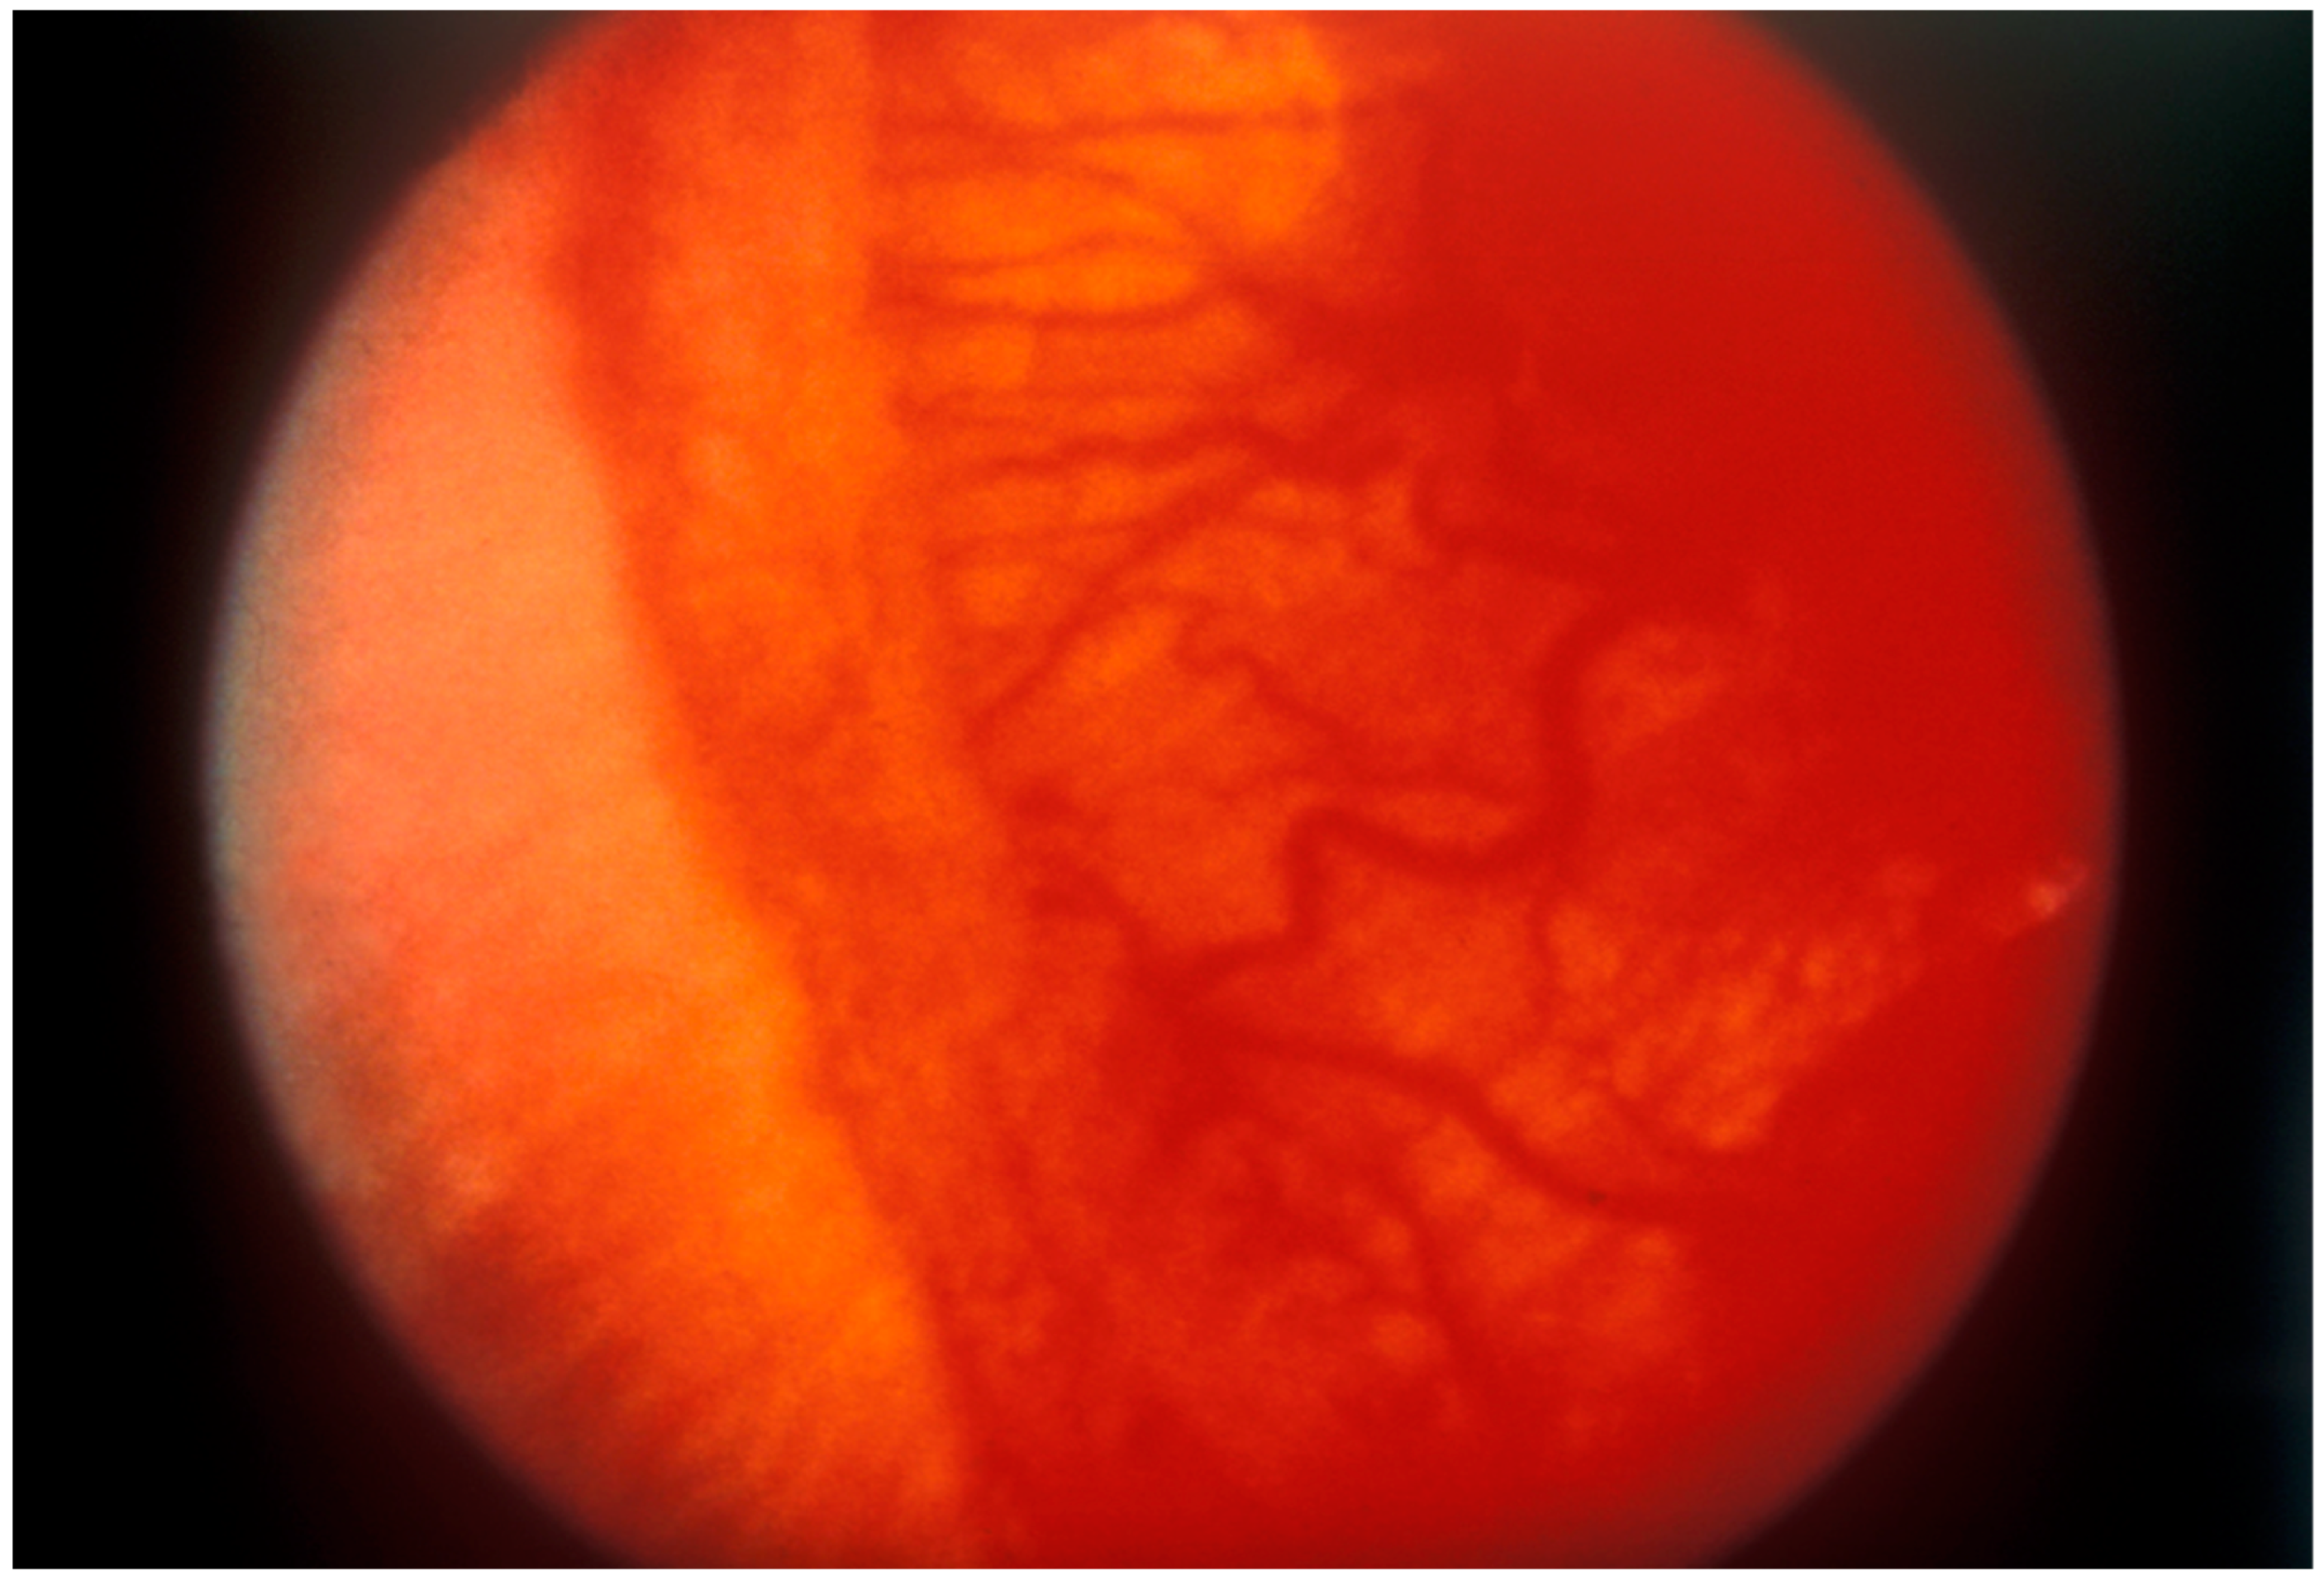

2. Overview of Retinopathy of Prematurity (ROP)

3.1. Cryotherapy

3.2. Laser Photocoagulation

3.3. Anti-Vascular Endothelial Growth Factor Therapy